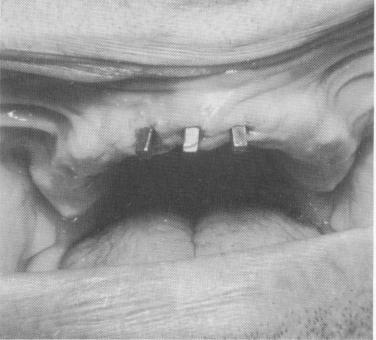

The template was cemented into position with hard cement placed inside the three anterior copings. Pin implants were driven through predetermined holes in the posterior extensions of the template and extended into the underlying alveolar bone to avoid the low-flaring maxillary sinus (Fig. 4-34). The pins were fused together in a series of three each with cold cure acrylic. The acrylic-covered pins were then prepared to form abutments (Fig. 4-35) . A full-arch acrylic-over-gold fixed denture was then fabricated and cemented over the template containing the three anterior gold cores and six acrylic cores.

Fig. 4-34. Pin implants were used posteriorly to avoid the maxillary sinus. Arrows point to copings covering vent-plants.

2 Endosseous pin implants used posteriorly to avoid maxillary sinus